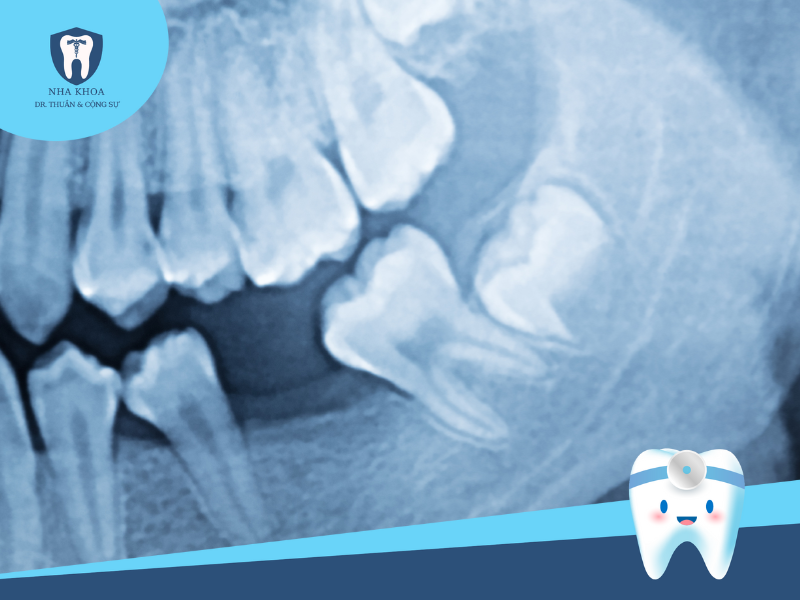

Bước 1: Khám tổng quát và chụp phim X-quang

Đây là bước đầu tiên nhưng cũng rất quan trọng trong quy trình nhổ răng khôn. Theo đó, nha sĩ sẽ thực hiện các biện pháp thăm khám để đánh giá tình trạng tổng quát, cũng như khám kĩ để xem xét tình trạng, vị trí, mức độ tổn thương... của răng. Sau đó, bác sĩ sẽ cho bệnh nhân chụp phim X-quang hàm răng để đánh giá hình ảnh chính xác về tư thế và vị trí răng khôn mọc, giúp nha sĩ nắm rõ và xây dựng kế hoạch nhổ răng phù hợp và ít sang chấn cho người bệnh.

Chụp X-quang xác định vùng răng cần cấy tủy

Răng khôn mọc lệch khi nhìn qua X-quang